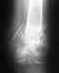

Насчет полной нагрузки - как-то по этим рентгенограммам это чересчур оптимистично.

Причём сказано это было абсолютно уверенно после первого же взгляда на снимки (правда, сначала было высказано несколько отборных крепких слов в адрес оперировавшего...). Может тут повлияло плохое качество репродукции и не всё видно на прикрепленном снимке?

Вот что в итоге получилось, снимки от 13 января 2010 года. В феврале убрали пластину, т.к. были боли в ноге в определенных ситуациях, например, при беге. Хотелось бы, если Вам не сложно, услышать оценку оставшейся деформации,насколько это критично в будущем (сейчас вроде всё ОК). Наверное, пора бы уже и позабыть, но всё ж терзают смутные сомнения, правильно я поступил, что не стал переделывать...Спасибо заранее.

Кликните для загрузки файла 1.jpg